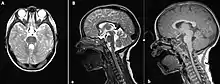

The disorder is characterized by absence or underdevelopment of the cerebellar vermis and a malformed brain stem (molar tooth sign), both of which can be visualized on a transverse view of head MRI scan.[15] Together with this sign, the diagnosis is based on the physical symptoms and genetic testing for mutations. If the gene mutations have been identified in a family member, prenatal or carrier diagnosis can be pursued.[4]